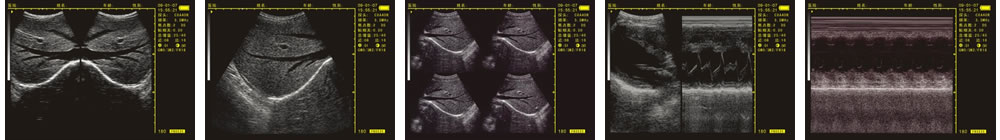

優(yōu)質的成像效果

V-20掌上B型超聲診斷儀(動物版)一流的數(shù)字成像技術,圖像更清晰